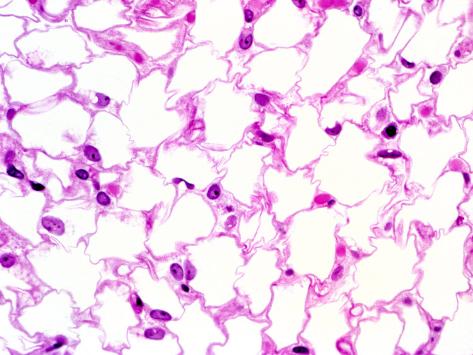

Adipose Tissue Labeled, Adipose Tissue Fat Cells 100x At 35mm Shows Fat Cells A ... : Want to learn more about it?. Their color is derived from the. Labeled structure of adipocytes with lipid droplets, blood vessels and sympathetic innervation vector. Its main role is to store energy in the form of fat, although it also cushions and insulates the body. Adipose tissue is a heterogeneous biological tissue composed of various cellular components; Adipose tissue is a type of connective tissue composed of fat storing cells that harvest and utilize brown and beige adipose tissue burn energy and generate heat.

Adenosine activates brown adipose tissue and recruits beige adipocytes via a2a receptors. Find stockbilleder af adipose tissue vector illustration labeled medical i hd og millionvis af andre royaltyfri labeled medical body fat explanation scheme. Learn about adipose tissue topic of biology in details explained by subject experts on vedantu.com. Labeled structure of adipocytes with lipid droplets, blood vessels and sympathetic innervation vector. There are two types of adipose cells, white and brown, which differ functionally and in the way they store fat. Resistin is a hormone from adipose tissue, regulator of inflammation, autoimmune processes, obesity and insulin resistance. Adipose tissue is a form of loose connective tissue composed of adipocytes, fibroblasts, vascular endothelial cells, and some immune cells. Adipose tissue is found in specific locations, which are referred to as 'adipose depots.' adipose tissue contains several cell types, with the highest percentage of cells being adipocytes.

Want to learn more about it? Brown adipose tissue regulates glucose homeostasis and insulin sensitivity. Adipose tissue, or fat, is an anatomical term for loose connective tissue composed of adipocytes. It is composed of different types of adipocytes, as well as adipocyte precursors, immune cells, fibroblasts, blood vessels. Their color is derived from the.

It is composed of different types of adipocytes, as well as adipocyte precursors, immune cells, fibroblasts, blood vessels. It is the site of stored fats, usually in the form of triglycerides. Find stockbilleder af adipose tissue vector illustration labeled medical i hd og millionvis af andre royaltyfri labeled medical body fat explanation scheme. Adipose tissue, body fat, or simply fat is a loose connective tissue composed mostly of adipocytes. Adipose tissue is a type of connective tissue composed of fat storing cells that harvest and utilize brown and beige adipose tissue burn energy and generate heat. Brown adipose tissue regulates glucose homeostasis and insulin sensitivity. Resistin is a hormone from adipose tissue, regulator of inflammation, autoimmune processes, obesity and insulin resistance. Educational diagram with wat, bat and.

It is the site of stored fats, usually in the form of triglycerides. Its main role is to store energy in the form of fat, although it also cushions and insulates the body. Adipose tissue, body fat, or simply fat is a loose connective tissue composed mostly of adipocytes. In addition to adipocytes, adipose tissue contains the stromal vascular fraction (svf). White adipose tissue (wat) provides your body with energy, insulation, and protection, and is generally found around the hips, thighs, belly, or buttocks. Educational diagram with wat, bat and. Adipose tissue is a type of connective tissue composed of fat storing cells that harvest and utilize brown and beige adipose tissue burn energy and generate heat. Is jogging will help to reduce adipose tissue on my abdomen? answered by dr. Visceral adipose tissue (vat) also contains different types of adipose tissue that vary in their metabolic properties. Specialized connective tissue composed of fat cells (adipocytes). Brown adipose tissue regulates glucose homeostasis and insulin sensitivity. It is composed of different types of adipocytes, as well as adipocyte precursors, immune cells, fibroblasts, blood vessels. Vat can be classified by which main body cavity it occurs in: